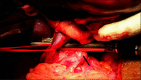

Backgrounds/aims: Proximal splenorenal shunt (PSRS) is considered a one-time treatment for noncirrhotic portal hypertension (NCPH) to prevent recurrent upper gastrointestinal (UGI) hemorrhage and long-term complications. Long-term shunt patency is necessary to achieve these. The lie of the shunt is a contributing factor to early shunt thrombosis. We investigated the role of resection of the distal tail of pancreas (caudal pancreatectomy [CP]) in improving the lie of shunt and decreasing shunt thrombosis.

Methods: This was a retrospective cohort study of patients with NCPH who underwent PSRS between 2014-2020 in JIPMER, Puducherry, India. CP was performed in patients with a long tail of pancreas, with the tip of pancreatic tail extending up to splenic hilum on preoperative CT. Perioperative parameters and shunt patency rate of patients who underwent PSRS with CP (Group A) were compared with patients undergoing conventional PSRS (Group B). Statistical analysis was performed using the Mann-Whitney U test and χ2 test.

Conclusions: CP is a safe and useful technique for reducing shunt thrombosis after PSRS in patients with NCPH by improving the lie of shunt.